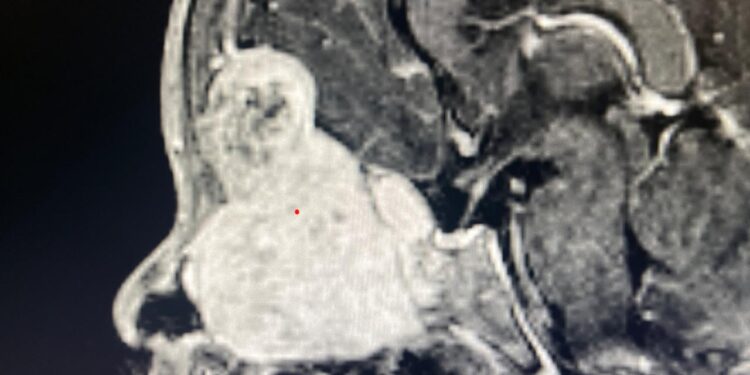

Sidhivinayak taimes Shimla। In a groundbreaking medical achievement, surgeons at PGIMER, Chandigarh have successfully removed a giant 7 cm skull base meningioma  from a 2-year-old child using only endoscopic techniques, marking a world first. The young patient from Sonipat, Haryana, had been suffering from a protruding left eye, restricted eye movement, snoring, and a nasal mass. Imaging revealed a massive tumor extending from the skull base into the nose, sinuses, orbit, and brain. Given the child’s age and the tumor’s complexity, the surgery posed extreme risks, including blood loss, hypothermia, and fluid imbalance.

A specialized team of neurosurgeons, ENT specialists, anesthesiologists, and nursing staff collaborated on the meticulous 9-hour procedure. Using advanced endoscopic tools, angled instruments, navigation systems, and innovative techniques to access the tumor through the nose, the team successfully removed it entirely without open surgery. Post-operative scans confirmed total excision, and the child is recovering well. Experts say this milestone underscores the world-class surgical expertise and innovation at PGIMER, setting a new benchmark in pediatric neurosurgery.